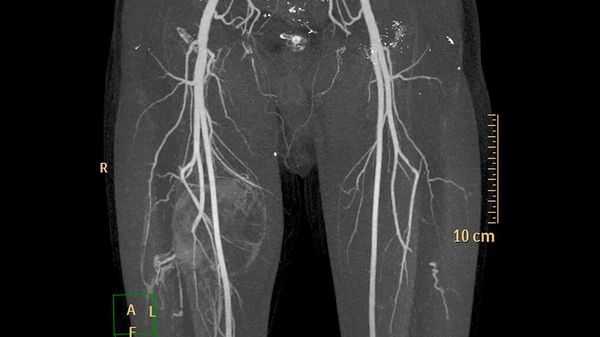

- ультразвуковое исследование (УЗИ) и магнитно-резонансную томографию (МРТ) для первоначальной диагностики [12] ;

- рентгеноконтрастную флебографию (введение в просвет вен рентгеноконтрастного вещества) для планирования лечения [7] .